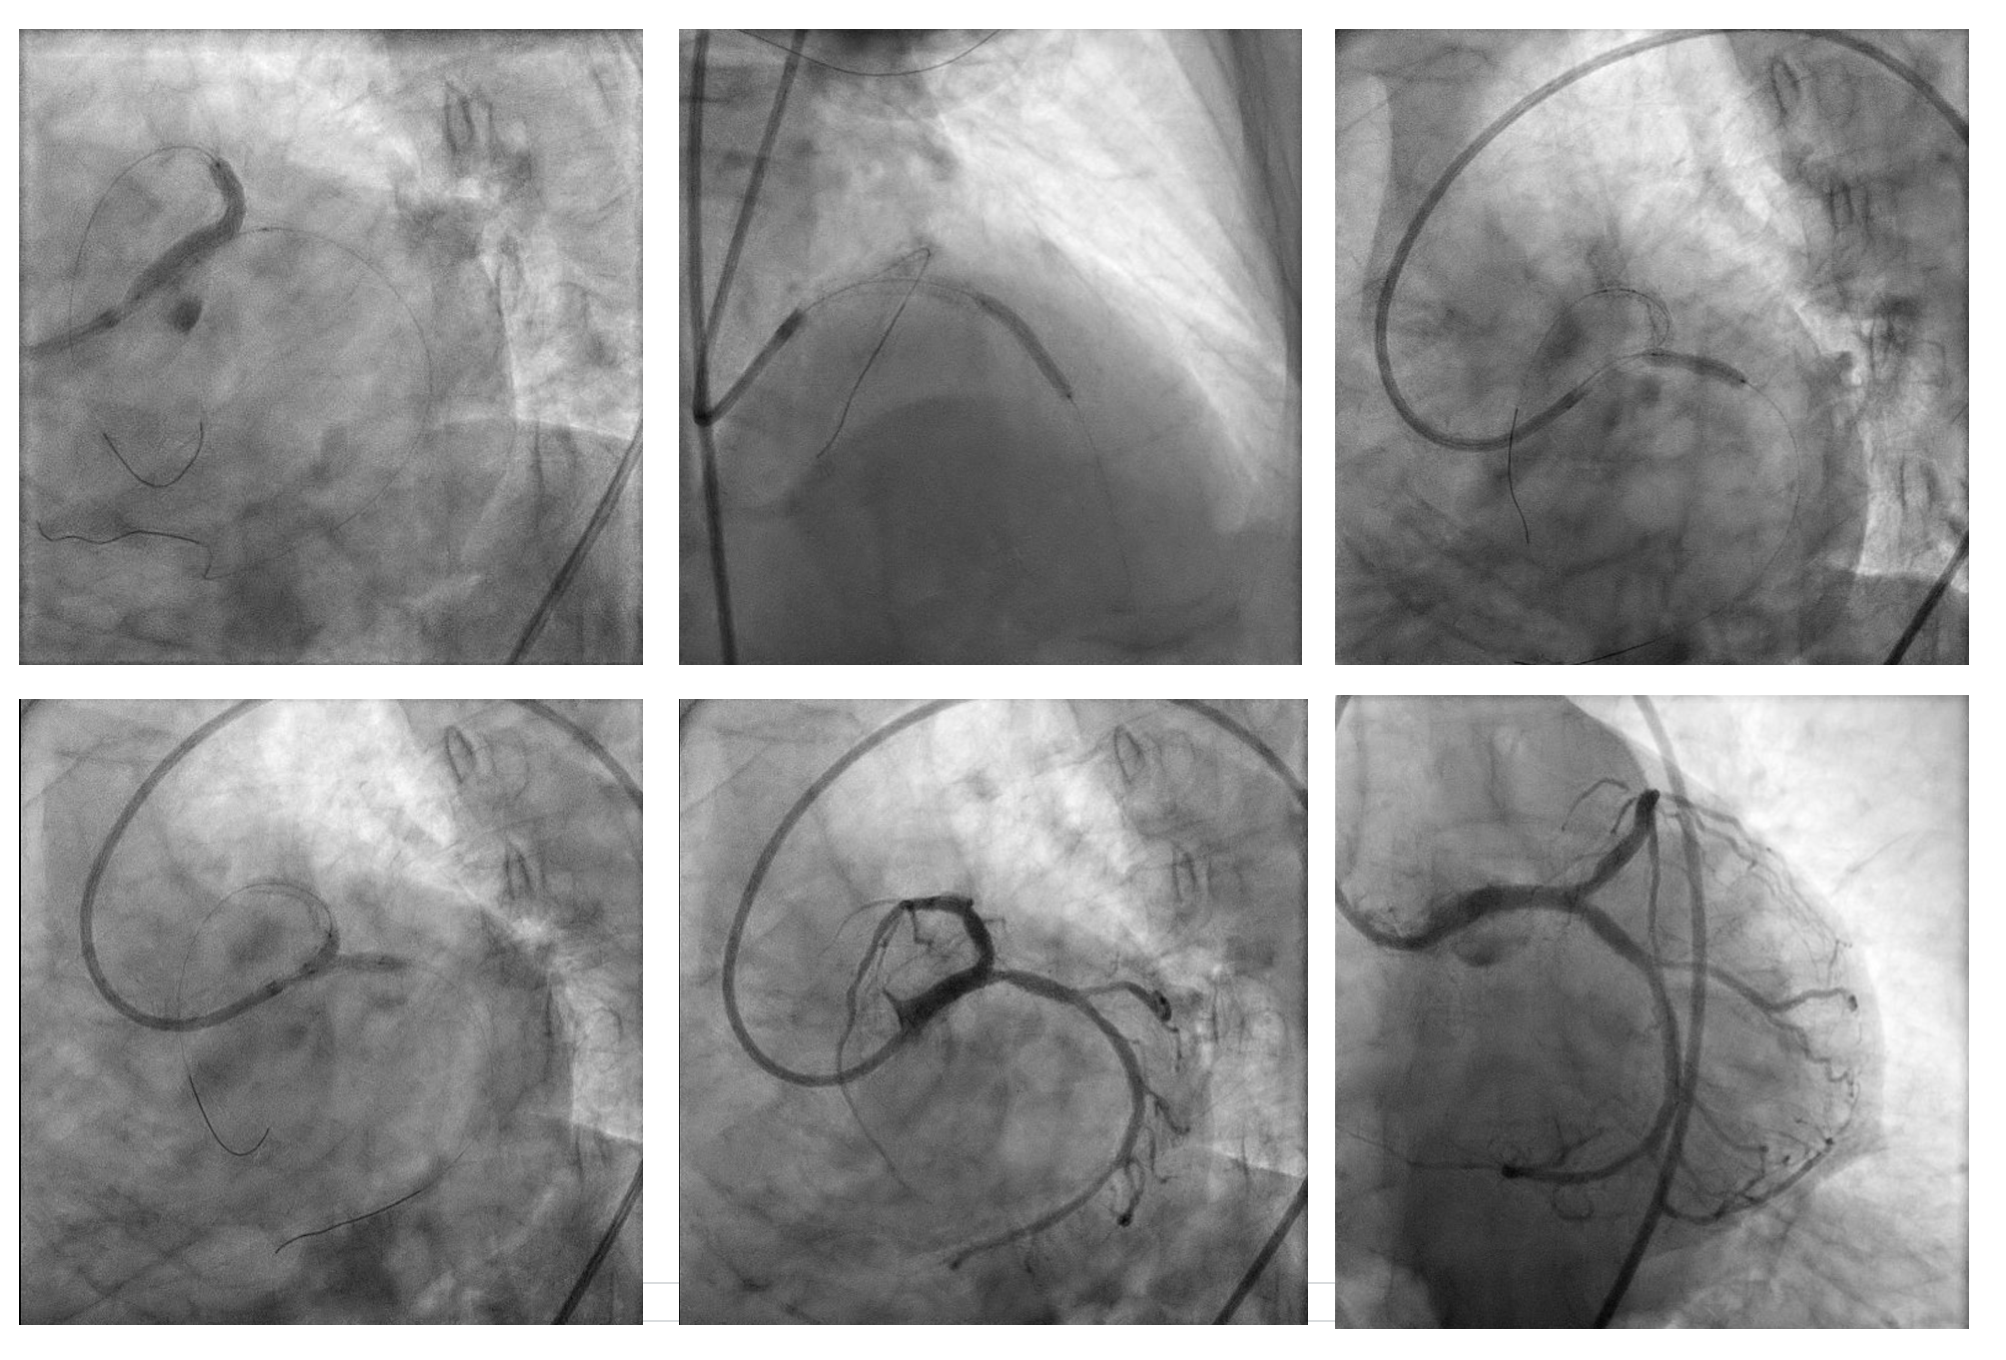

A second stent (Promus Premier 2.75 ¡¿ 24 mm) was implanted in proximal–mid LAD overlaping with previous stent, then high-pressure post-dilatation and POT (NC 4.5¡¿8 mm) was performed. LCx was rewired and treated with TAP stenting (Promus Premier 3.5 ¡¿ 18 mm) after sequential and final kissing balloon dilatations. Post-IVUS confirmed well-expanded and well-apposed stents (MSA LAD 5.22 mm©÷; LCx 7.82 mm©÷).

Final angiogram showed TIMI 3 flow with no residual dissection. Procedure duration 30:52 min; contrast 180 mL; DAP 117.05 Gy¡¤cm©÷.